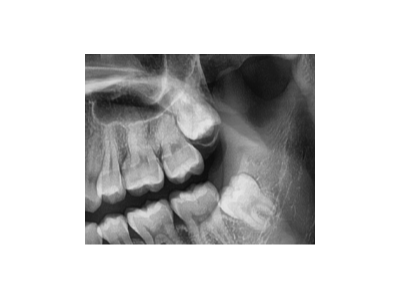

河北惟德口腔醫(yī)院告訴大家多數(shù)的成年人,經(jīng)常會(huì)發(fā)現(xiàn)自己牙齒內(nèi)側(cè)有牙結(jié)石、牙垢的情況,對(duì)于這類的牙齒問(wèn)題其實(shí)是需要及時(shí)洗牙的,因?yàn)檫@些局部刺激會(huì)不斷的刺激牙齦,對(duì)于整體的口腔健康是非常不利的。對(duì)于洗牙結(jié)石…

惟德口腔告訴大家,小孩因?yàn)楸旧淼娘嬍沉?xí)慣以及口腔牙齒發(fā)育的原因,導(dǎo)致不少孩子都有蛀牙問(wèn)題,兒童蛀牙問(wèn)題其實(shí)只要及時(shí)發(fā)現(xiàn)并且及時(shí)的治療,一般情況下影響不大,但是仍然不能忽略,不少家長(zhǎng)在這方面有一定的了解…

河北惟德口腔醫(yī)院小編提醒大家,牙齒牙縫變大,不僅影響我們正常的口腔牙齒健康以及平衡,而且還直接影響我們的正常生活飲食以及面部顏值。當(dāng)然這里面導(dǎo)致牙齒牙縫變大的原因有很多,不同原因的后果以及影響是不同的…

寶寶牙疼去承德哪家牙科治療比較好呢?牙疼的問(wèn)題不僅僅是很多成年人、老年人身上會(huì)出現(xiàn),實(shí)際上不少的小孩子也會(huì)出現(xiàn)牙疼的問(wèn)題,寶寶牙疼家長(zhǎng)們比較擔(dān)心,一般這種牙疼主要是蛀牙引起的。那么承德哪家牙科類似的治…